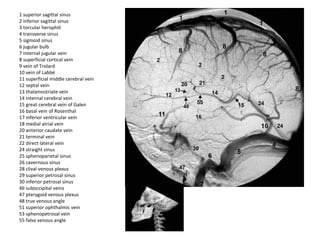

1 superior sagittal sinus

2 inferior sagittal sinus

3 torcular herophili

4 transverse sinus

5 sigmoid sinus

6 jugular bulb

7 internal jugular vein

8 superficial cortical vein

9 vein of Trolard

10 vein of Labbé

11 superficial middle cerebral vein

12 septal vein

13 thalamostriate vein

14 internal cerebral vein

15 great cerebral vein of Galen

16 basal vein of Rosenthal

17 inferior ventricular vein

18 medial atrial vein

20 anterior caudate vein

21 terminal vein

22 direct lateral vein

24 straight sinus

25 sphenoparietal sinus

26 cavernous sinus

28 clival venous plexus

29 superior petrosal sinus

30 inferior petrosal sinus

46 suboccipital veins

47 pterygoid venous plexus

48 true venous angle

51 superior ophthalmic vein

53 sphenopetrosal vein

55 false venous angle